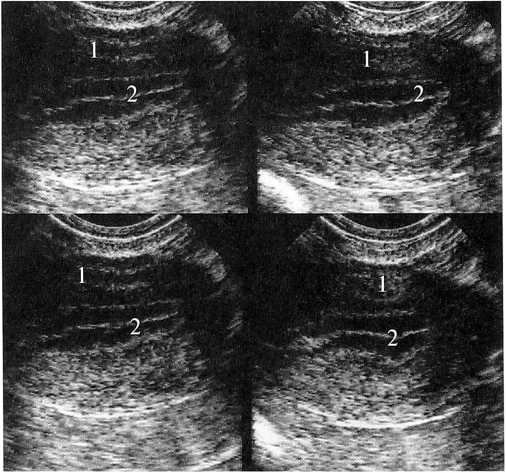

Из 314 обследованных женщин изменения в эндометрии были выявлены у 294 (93,63%). Гиперплазия и полипы эндометрия встретились у 20 (6,37%) женщин, рак эндометрия наблюдался в 3 (0,96%) случаях, субмукозные миомы матки были выявлены у 32 (10,19%) пациенток. У остальных 239 (76,11%) женщин с клиническими проявлениями НМЦ в эндометрии наблюдались локальные участки железистой или железистокистозной гиперплазии. Возраст пациенток составил от 21 до 45 лет (средний возраст 37,5 года). Женщины предъявляли жалобы на: увеличение продолжительности менструации, обильные менструации, кровомазанье в середине цикла. В эндометрии определялись гиперэхогенные дисфункциональные образования — локальные участки гиперплазии (ЛУГ); в яичниках выявлялись фолликулярные кистовидные образования от 6 до 15 мм и фолликулярные кисты от 25 до 40 мм в диаметре. Образования в эндометрии были одиночными в 231 (96,65%) случаях и множественными в 8-ми (3,35%) наблюдениях. Размер ЛУГ в наибольшем измерении (длинник) составлял от 2,6 до 0,4 см в среднем (1,2±0,4 см), в наименьшем (поперечник) — от 1,2 до 0,3 см (в среднем 0,6±0,3 см). Располагались они центрально — в середине полости матки (рис. 1) или в ее дне (рис. 2) по срединной линии соприкосновения передней и задней стенок матки (средняя из трех гиперэхогенных линий) — структура эндометрия имела сниженную эхогенность, соответствующую пролиферативной фазе (рис. 1, 2), но с разной степенью влияния секреторной фазы. Эхогенность образований была высокой — соответствующей эхогенности эндометрия в секреторную фазу.

Рис. 1. Больная К. 36 лет. 11 день МЦ.

ЛУГ в эндометрии в середине полости матки. Продольное ТВ-сканирование. 1 — матка, 2 — М-эхо с ЛУГ (УЗ картина напоминает одиночный полип эндометрия)

Контуры ЛУГ были ровные, четкие, как бы подчеркнутые, каждое из образований было окружено тонкой равномерной по толщине гиперэхогенной полоской, которая «как бы» огибала его с двух сторон и плавно переходила в неизмененный центральный отдел эндометрия — срединную гиперэхогенную линию (см. рис. 1, 2).

Рис. 2. Больная С. 35 лет. 13 день МЦ.

ЛУГ в эндометрии в дне полости матки. Продольное ТВ-сканирование. 1 — матка, 2 — М-эхо с ЛУГ (УЗ картина напоминает одиночный полип эндометрия)

Этот признак прослеживался как в 1-ю, так и во 2-ю фазы МЦ (рис. За) у всех 232 женщин. Форма ЛУГ была правильная: округлая или овальная, структура — однородной, без наличия кровотока как в центре, так и по его периферии. При исследовании на 4-6 день МЦ (рис. 3б) отмечалось значительное уменьшение образования до 0,6—0,2 см (по длиннику) и до 0,3—0,2 см (по поперечнику). Однако к 8-10 дню МЦ образование в эндометрии имело ту же форму и размеры и практически не менялось до наступления следующей менструации.